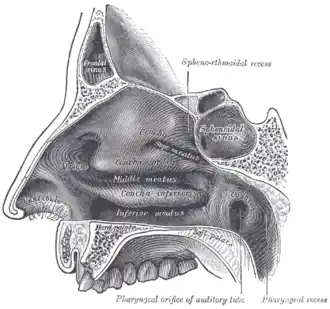

Lateral wall of nasal cavity. | |

Boundaries

A choana is the opening between the nasal cavity and the nasopharynx.

It is therefore not a structure but a space bounded as follows:

- anteriorly and inferiorly by the horizontal plate of palatine bone,

- superiorly and posteriorly by the sphenoid bone

- laterally by the medial pterygoid plates.

- medially by the Vomer